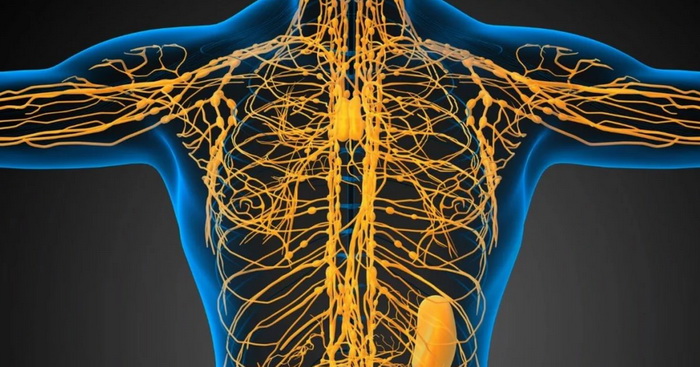

Изображения и схемы: как выглядит лимфа